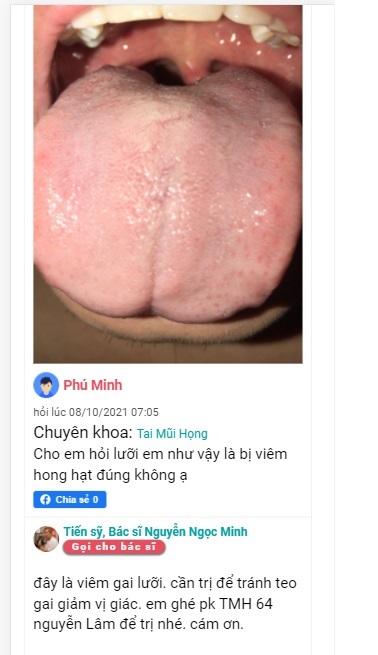

Tiến sỹ, Bác sĩ Nguyễn Ngọc Minh

Giảng Viên chuyên khoa TMH Trường Đại Học Y khoa Phạm Ngọc Thạch